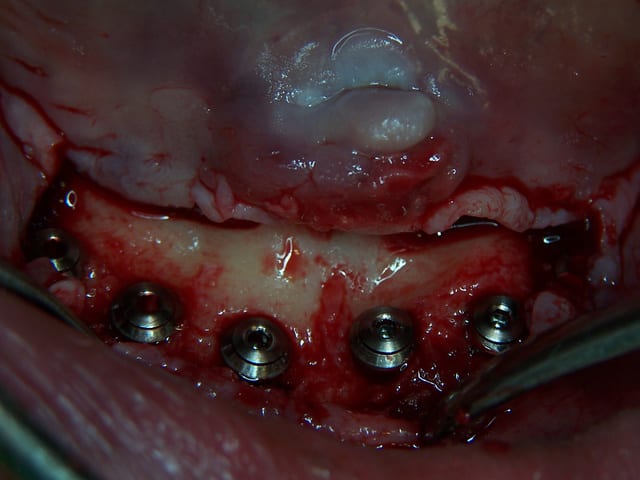

sauf que la semaine prochaine on lui pose le 7 ième et le 8 ième implant !

j'aurai jamais cru cela possible avec aussi peu d'os.

en bas 5 implants symphysaires et en haut, greffes d'apposition pour 4 implants de chaque côté.

8 implants maxillaire

et possiblement 5+2 mandibulaire

à priori sans greffe (expansion), mais pas sans effort!